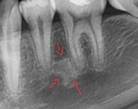

1 |

Osteítis condensante |

Asintomático lesión radiopaco-difusa con masa más o menos definido asociado al ápice del diente afectado se ve esclerótica no expandible.5 |

|

|||

2 |

Osteoesclerosis idiopática |

Lesión radiopaca localizada asintomática no expansiva masa irregular redonda o elíptica o sea bien definida.6 |